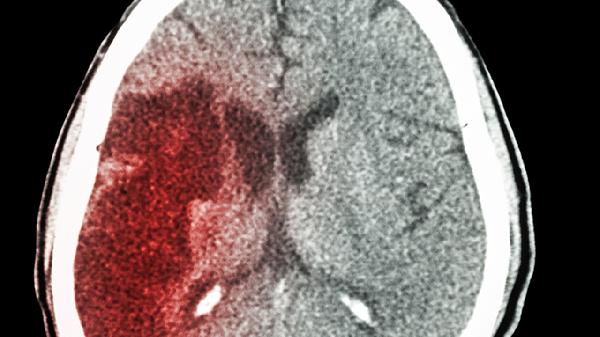

脑梗后出现视力下降的情况,可以通过视觉训练、药物治疗、手术干预、中医调理以及营养支持等多种方式来改善。这种视力问题通常是由视神经受损、视网膜供血不足或大脑视觉区域功能障碍等引起的。